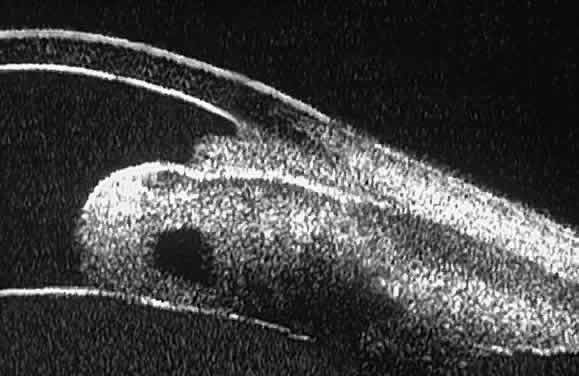

Fig. 18 . Localization of posterior chamber IOL haptics by UBM. A. Haptic in capsular bag (arrow). B. Haptic (bright object just behind peripheral iris) in iridociliary sulcus. Fig. 18 . Localization of posterior chamber IOL haptics by UBM. A. Haptic in capsular bag (arrow). B. Haptic (bright object just behind peripheral iris) in iridociliary sulcus.

|